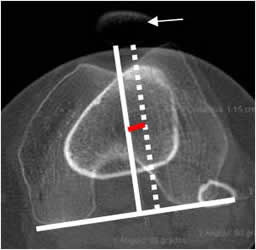

Torsión tibial:

Medido mediante TAC, con cortes axiales que se superponen. Uno sobre la tuberosidad tibial y otro en el tobillo, a nivel de la base de los maleolos. (3).

La tibia tiene una retroversión externa normal, de 15º a 20º en los adultos. (3).

El ángulo se forma por la línea tangente a la epífisis tibial posterior y el eje bimaleolar del tobillo. Su valor promedio es de 35º. (18, 22). (Fig 80 y 81).

Fig 80. Torsión tibial.

A: TAC axial a nivel de la espina tibial y línea que pasa por la parte posterior de la tibia.

B: TAC axial, con línea sobre el eje bimaleolar del tobillo.

Se superponen y forman el ángulo de torsión tibial.

Fig 81. Torsión tibial.

Medición del ángulo con el software de la máquina.